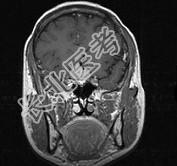

单项选择题女,32岁, 右眼视物模糊1年,加重2月, 请根据所提供图像,选择最可能的诊断是 ( )

A、鞍区转移瘤

B、鞍区海绵状血管瘤

C、鞍区动脉瘤

D、鞍区垂体瘤

E、鞍区脑膜瘤